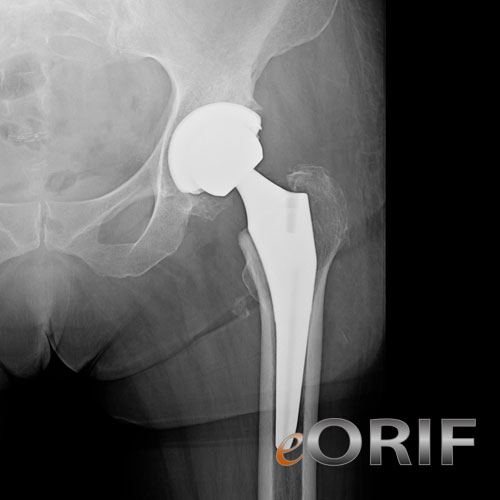

Anterior hip replacement xray